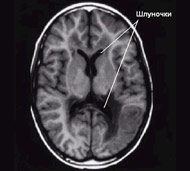

Консистенція головного мозку нагадує желе, яке, наче, плаває в черепі, наповненому спинномозковою рідиною. Ця рідина також заповнює великі порожнисті структури, які називаються шлуночками і які розташовані в глибині головного мозку.

Спинномозкова рідина проходить через шлуночки, що є системою сполучених посудин та каналів. Потім рідина потрапляє в закриті простори, розташовані між головним мозком і черепом, де вона поглинається кровотоком.

Збалансовані утворення, циркуляція і поглинання спинномозкової рідини мають важливе значення для підтримання нормального тиску в черепі. Гідроцефалія розвивається тоді, коли відтік спинномозкової рідини порушений, наприклад, при звуженому каналі між шлуночками або при порушенні абсорбції рідини організмом.

Порушення абсорбції спинномозкової рідини викликає розвиток нормотензивної гідроцефалії, що найчастіше спостерігається у літніх людей. При нормотензивній гідроцефалії надлишкова рідина розширює шлуночки, але не підвищує тиск, який впливає на головний мозок. Нормотензивна гідроцефалія може виникнути внаслідок травми або захворювання, але в більшості випадків причини її виникнення невідомі.